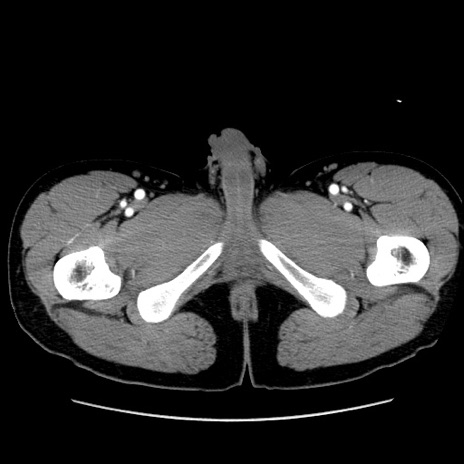

冠状断像

【症例】20歳代 男性

【主訴】心窩部痛

【現病歴】今朝より上腹部痛あり。一旦軽快していたが再度出現したため救急要請。昨日夕に白身の魚を含む刺身を食べた。

【身体所見】BP 136/89mmHg、HR 74/min、BT 37.0℃、腹部:膨満、軟、心窩部に圧痛あり。反跳痛なし、筋性防御なし、腸雑音やや亢進あり。

【データ】WBC 17700、CRP 0.48